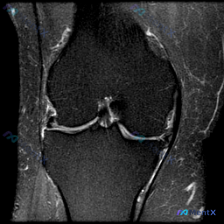

拿到这份病例和影像,先整理一下所有信息,再梳理思路: 一、核心临床问题 本次提出的核心疑问是:判断是否存在半月板异常 二、现有影像学发现(膝关节MRI T2序列冠状位单层面) 我先把所有客观发现整理出来: 1. 骨骼与关节软骨:股骨远端、胫骨近端骨皮质连续,无骨折;骨髓信号均匀,无明显水肿/硬化;关...

看到一份膝关节MRI的影像资料,问题是观察半月板异常,整理一下完整分析思路分享给大家。 病例基本影像信息 这是一份膝关节冠状位T1加权MRI的单影像分析,核心异常聚焦在半月板: 1. 骨骼结构:股骨远端、胫骨近端骨质信号均匀,无骨髓水肿、骨质破坏,皮质连续完整 2. 关节软骨:关节面软骨形态规整,无...

看到一个有意思的影像讨论病例,整理一下资料和思路分享给大家。 病例背景 提问:单张膝关节冠状位MRI图像,问题是图像中可见的异常是什么,提示半月板异常。 影像初步分析 先确认这张影像的基本信息:这是膝关节冠状位MRI,对比良好,骨髓信号正常,可以看到股骨远端、胫骨近端、内外侧关节间隙、半月板和侧副韧...